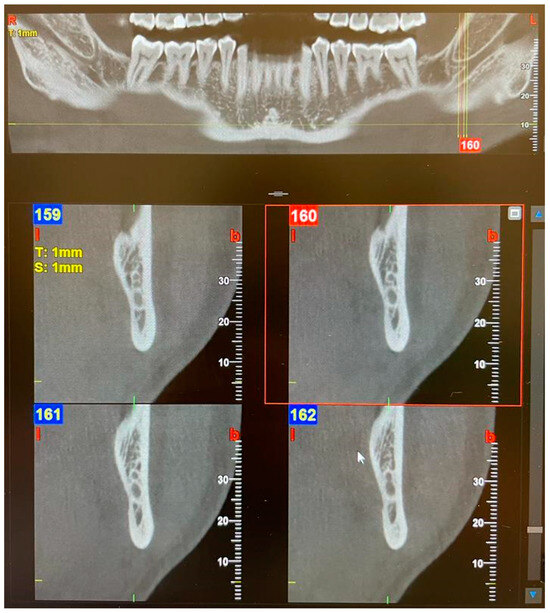

Figure 3. Panoramic view and transverse section of a left Type 3—Forward BMC with confluence. l, lingual. b, buccal. T, thickness. S, section.